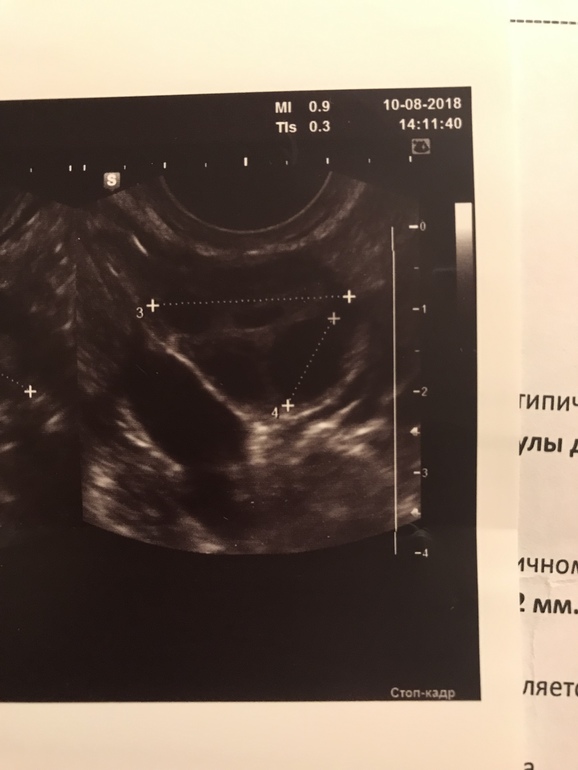

вот так выглядит ДФ

И вот ЖТ.. правда не регресс, а свежее, но оно все равно как-то иначе выглядит)) здесь диаметр его 17мм

оно рябое какое-то

В жт типа такая сеточка должна быть, а полностью чёрное это фолликул